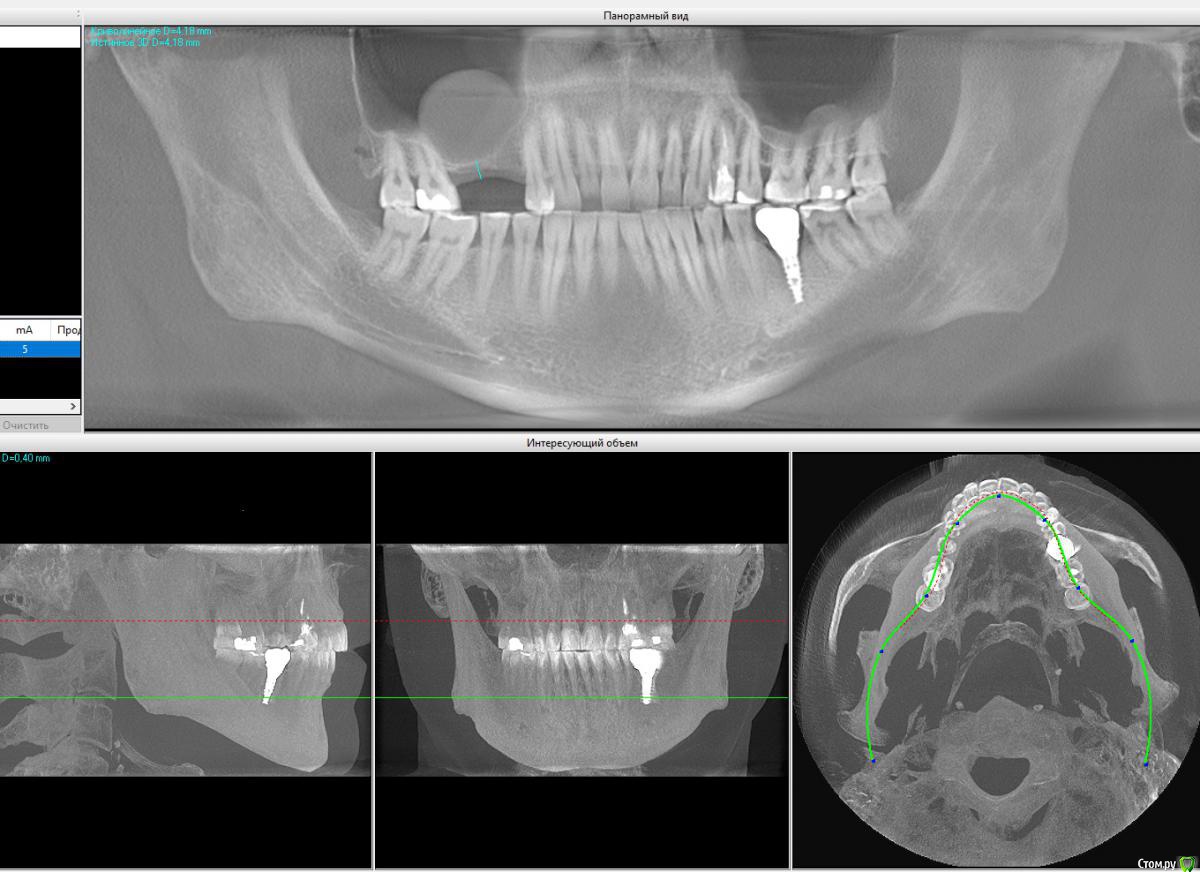

YuraK9 Опубликовано 14 февраля, 2019 Поделиться Опубликовано 14 февраля, 2019 Добрый день, нужна имплантация после удаления верхних 5,6, но над ними приличная киста. Мой стоматолог советует удалить кисту эндоскопически через нос, ждём, затем синус-лифтинг открытый, как я понимаю, ждём, затем имплантация. Есть ли достойные варианты уменьшить количество операций, что-то совместить между собой?Снимок с КТ прилагаю. Ссылка на комментарий